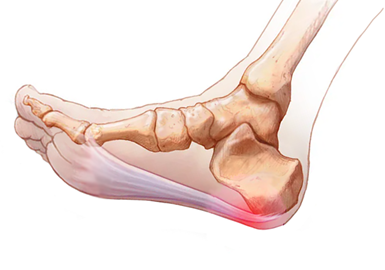

图1:引起足跟痛的解剖简图

图3:跖腱膜发生退变的部位

图4:跖筋膜炎的痛点